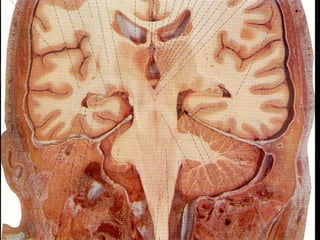

2. Cápsula Interna (AVC)

-Fraqueza completa, proporcional e contralateral. Alteração da sensibilidade